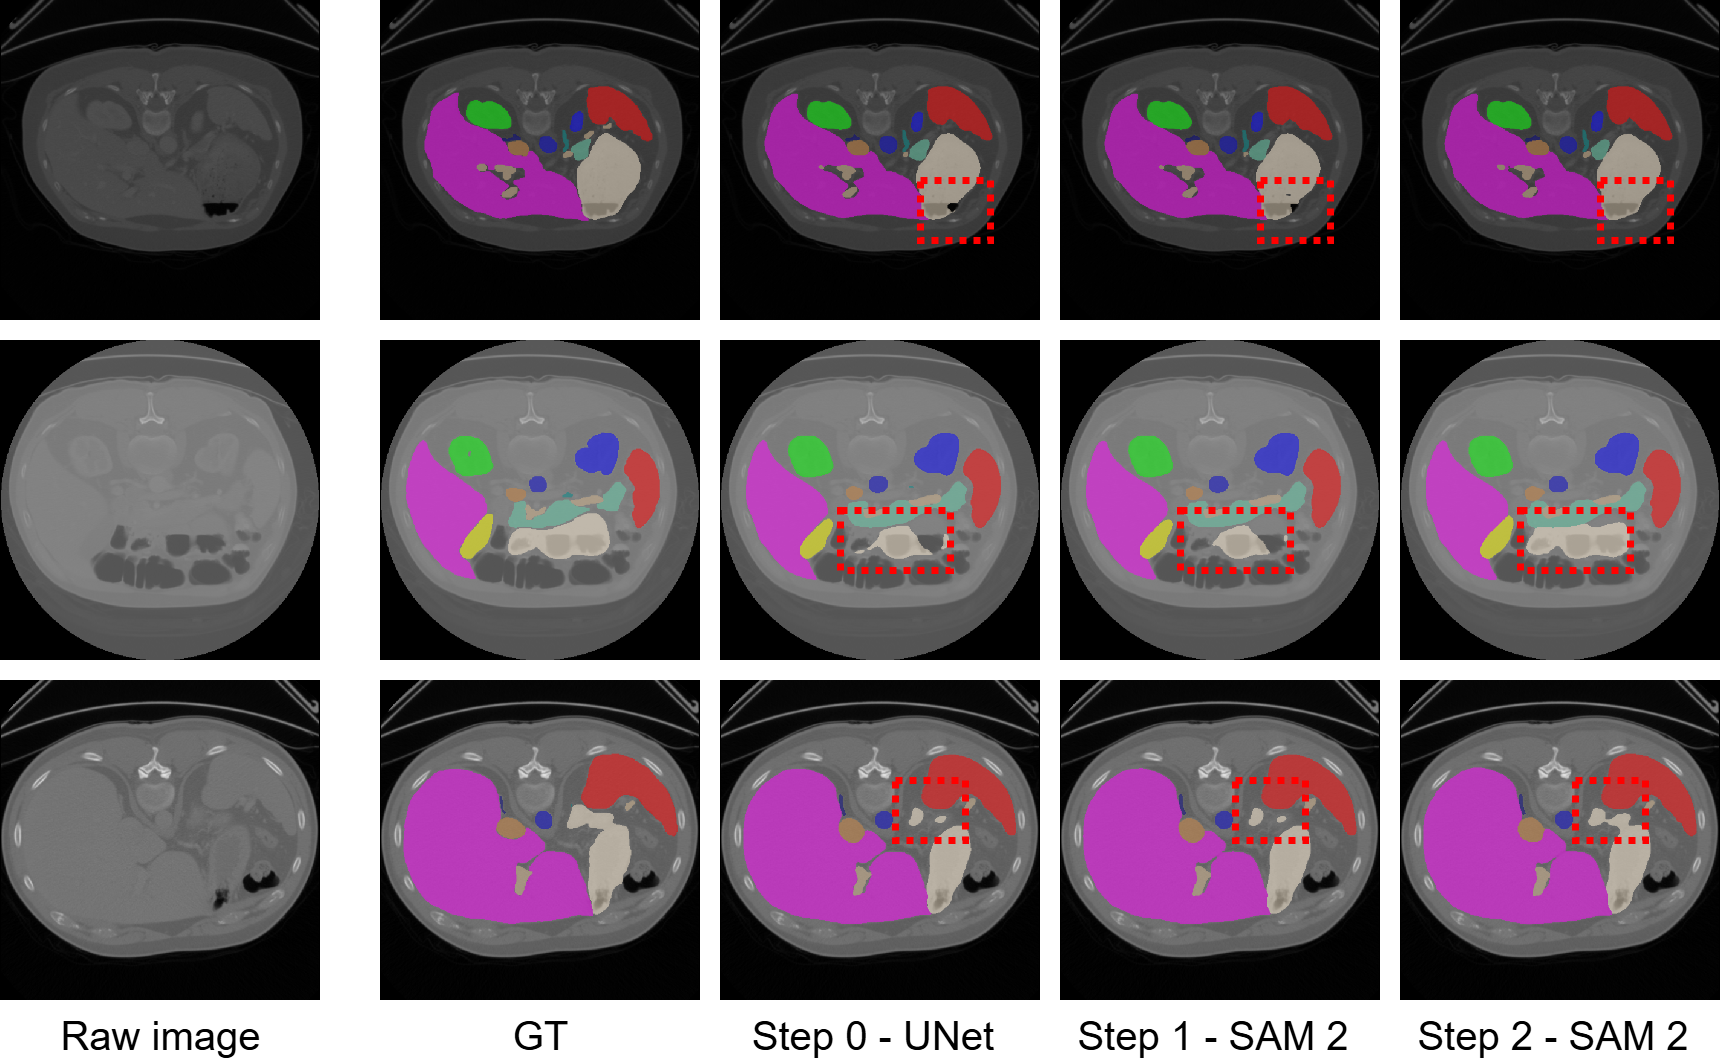

Refer to caption

Figure 4: Qualitative comparison on BTCV dataset. RFMedSAM 2 is the most precise for each class and has fewer segmentation outliers.

4.2.2 Results on the BTCV Dataset.

Table 3 shows the quantitative performance on the BTCV dataset, comparing RFMedSAM 2 with leading SAM-based methods with proper prompts(i.e., SAM [13], SAM2 [19], MedSAM [16], SAM-U [6], and SAM-Med2D [5]), SAM-based methods without prompts (i.e., SAMed [26] and SAM3D [1]), convolution-based methods (VNet [20] and nnUNet [11]), transformer-based methods (TransUNet [4], SwinUNet [3], and nnFormer [28]). We observe that RFMedSAM 2 outperforms all existing methods, setting a new state-of-the-art benchmark. When provided with proper prompts, RFMedSAM 2 achieves a DSC of 92.3%, representing a significant 5% improvement over the previous state-of-the-art method. In comparison, among SAM-based methods with the proper prompts, the best performance, achieved by SAM-Med2D, reaches only 84.7%. Our proposed RFMedSAM 2 surpasses this by 7.6%, highlighting its superior effectiveness over SAM-based methods with prompts. When prompts are not provided, our proposed prompt-free RFMedSAM 2 outperforms the other prompt-free SAMed and SAM3D by 9% and 6%, respectively. Compared with non-SAM-based methods, our method surpasses nnUNet and nnFormer by 6.4% and 1% in DSC for the highly saturated dataset. In Figure 4, we illustrate qualitative results compared to representative methods. These results also demonstrate that our RFMedSAM 2 can predict more accurately the ‘Stomach’, ‘Spleen’, and ‘Liver’ labels.

Figure 8: More visualization of two refinements.

12 More Visualization of Two Refinements

In Figure 8, we present additional qualitative results showcasing the refinements at different stages. With the two refinements, the results clearly illustrate the progressive improvement in segmentation accuracy, emphasizing the effectiveness of our model’s refinement process.